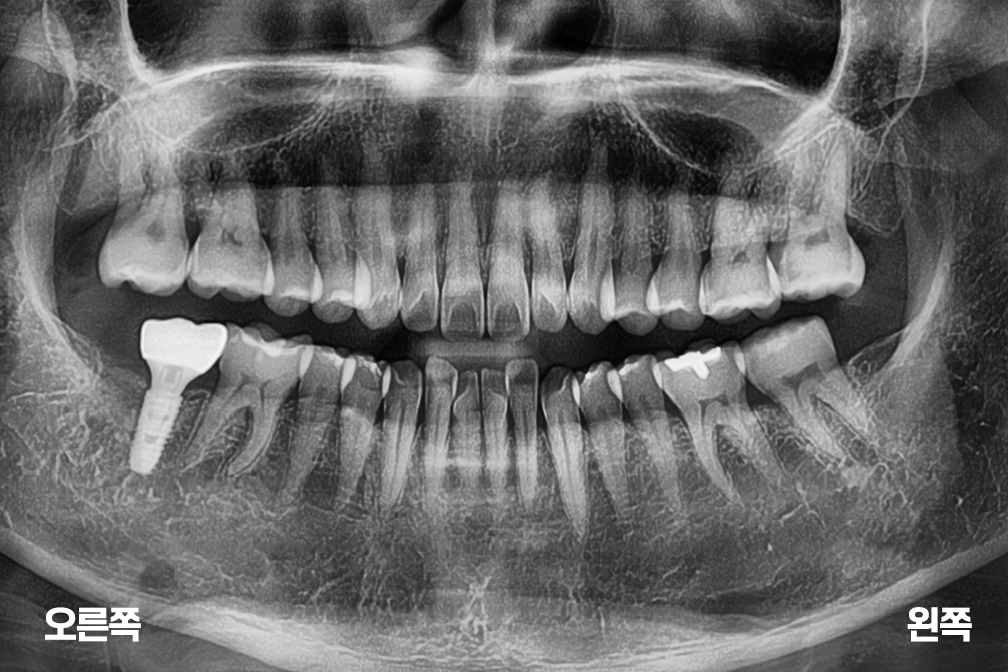

After 2026년 3월 6일